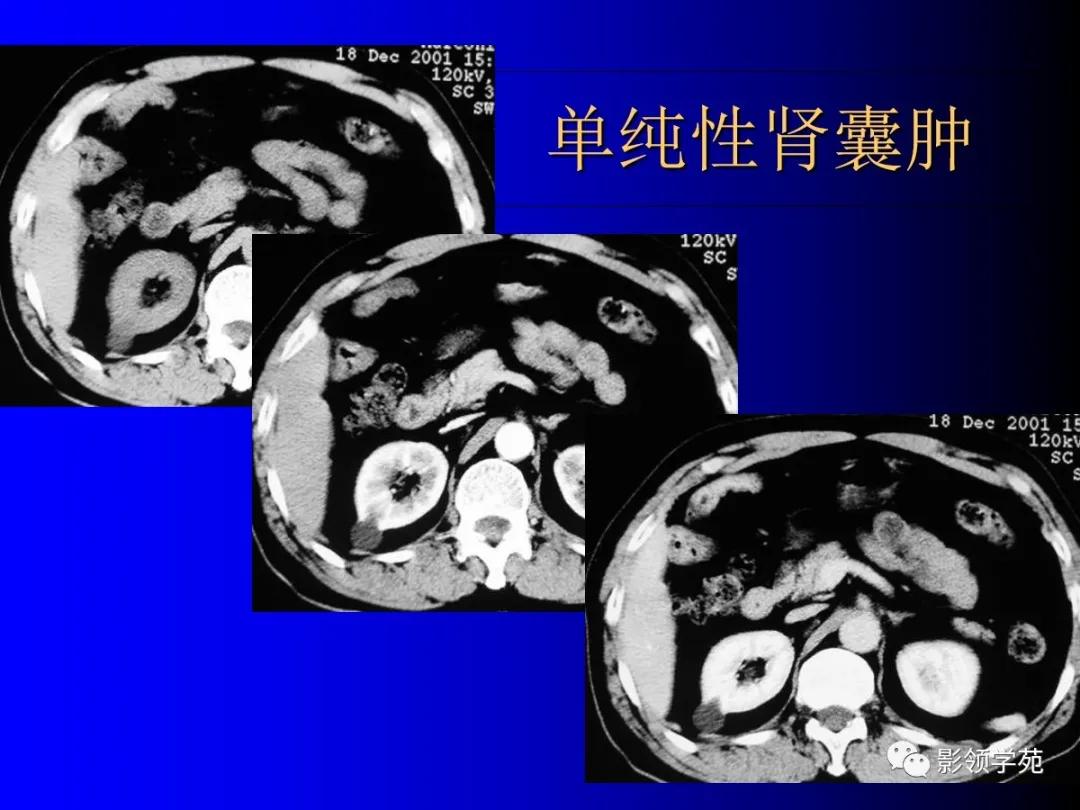

1、单纯性肾囊肿

位于肾皮质内的良性囊性病变。

常多发,大小不一。

呈圆形,壁菲薄光整,内衬扁平上皮,含清亮浆液。

囊肿可位于肾内或突出于肾轮廓外。

增强扫描无强化。

CT上可见单发或多发的肾囊肿,以单发的囊肿多见。单纯肾囊肿表现为囊肿壁光滑,增强扫描无强化。囊肿内容物呈水样密度。与单纯肾囊肿不同,由于肿瘤内部有出血,囊肿内可见不均匀的内容物,似呈棉絮状。囊肿壁不均,平扫时囊壁的密度为30~50Hu左右,增强后为50~90Hu。厚囊肿壁(大于1mm),且附着处存有实质性成分的CT征象提示肿瘤。由于单纯性肾囊肿可以恶变,因此,当囊肿壁突然增大,囊肿出现内容物时,要高度怀疑囊性肾癌。CT特别是薄层增强扫描是早期诊断囊性肾癌的可靠方法。